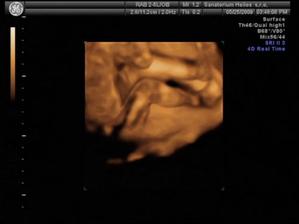

20.1.2009 - těhu potvrzeno od Dr. Máme první fotečku našeho "Prdýska"